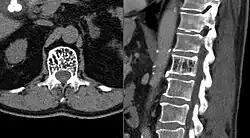

Axial and sagittal CT views of a vertebral hemangioma

CT

On computed tomography (CT) or radiograph, VHs can cause rarefaction with vertical striations (often referred to as corduroy pattern) or a coarse honeycomb appearance. A polka-dot appearance on CT scan represents a cross-section of reinforced trabeculae.[11][13] CT best defines the bony architecture and is the best diagnostic imaging method.[14]